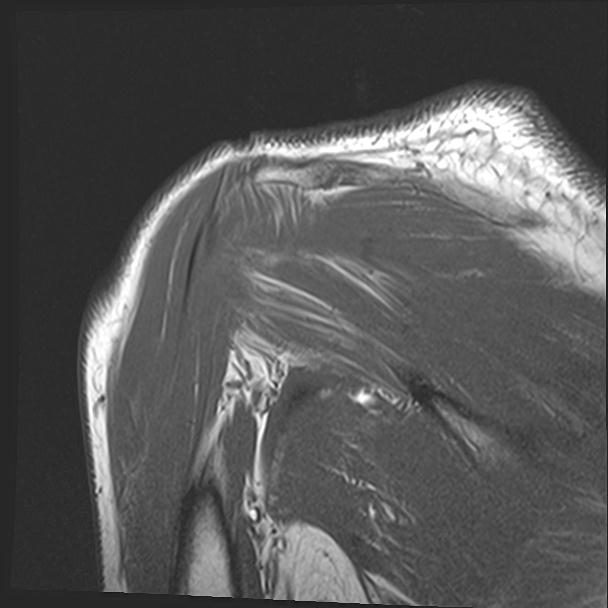

60058 3/9 11/4 右肩 2R+MRI 73歳男性 肩腱板損傷